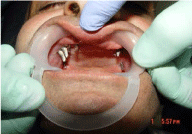

A 46 years old patient, presented to our clinic with a diagnosis of generalized periodontitis of the lower jaw, with edentulous atrophic maxilla. A comprehensive clinical and radiographic evaluation revealed advanced alveolar bone resorption rendering the prognosis of all lower teeth unfavorable. After the preliminary clinicalradiation examination, a treatment plan was defined that included the removal of all the teeth of the mandible and the installation of 8 dental implants in lower jaw, the installation of 1 dental implants in the tuber regions of the upper jawbone on both sides, the installation of 2 dental implants in zygomatic bone from both sides and installation 4 dental implants in the area of 13,14,23,24 distant teeth. 4 months after implant placement prosthetic restoration was fabricated and adjusted. The patient has been followed up for 5 years. So far, no further problem has occurred and the restoration has remained functional (Figures1-8).

Figure 3: Intraoral view of abutments upper jaw before prosthetic reconstruction

Figure 4: Intraoral view of abutments lower jaw before prosthetic reconstruction